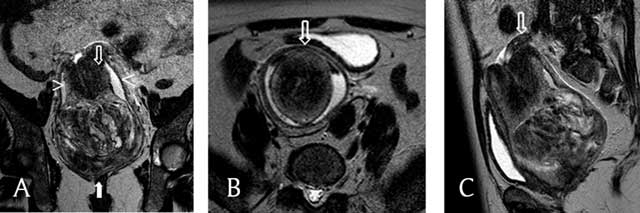

Figure 1

T2-weighted MRI (a, b, c) a. This coronal image shows a vaginal heterogeneous mass (filled arrow), with the uterine corpus in a U-shape above the mass (empty arrow). The cervix surrounds the corpus, and the vaginal fornix surrounds both the corpus and the cervix (arrowheads). b. This axial image shows, from the center outwards, the uterine corpus, the cervix, and the fornix and the invaginated round ligaments in a bullseye appearance (arrow). c. This sagittal image shows one ovary above the cervix (arrow).